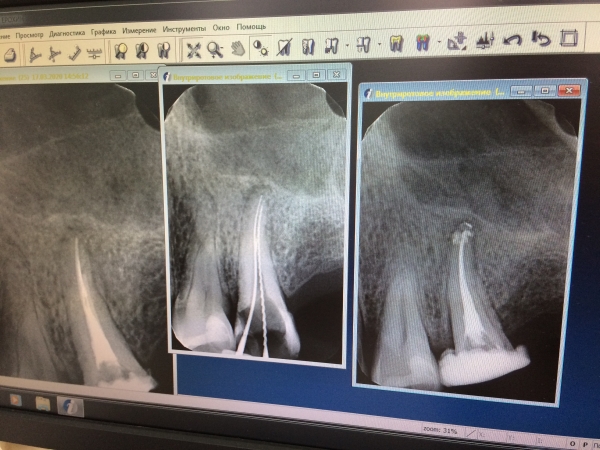

Прикладываю фото 25-го зуба (там 3 фото с иглами до пломбировки каналов и после один был не до пломбирован, сразу добавили на третьем фото. Небольшое воспаление у корня было, его лечили, сказали результат не сразу).

Можно ли на такой зуб поставить вкладку из диоксид циркония? Фактор двухканальности зуба облегчает ситуацию? Как фактор близости к десне и возможного контакта вкладки с тканями зуба влияет на выбор материала культевой вкладки? Можно ли уже заниматься протезированием? Как вы оцениваете лечение корневых каналов? Как относитесь к культевым вкладкам из титана? Какую вкладку мне установить вкладку? Бывают ли вкладки из чистого титана? Может ли быть возможный контакт культевой вкладки с тканями зуба причиной беспокойства?